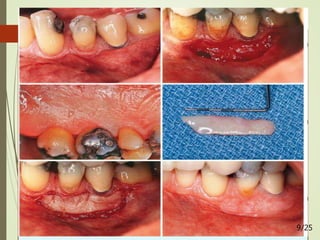

FREE CONNECTIVE TISSUE AUTOGRAFTS TO INCREASE

ATTACHED GINGIVA

20/25

2. FREE CONNECTIVE

TISSUE AUTOGRAFT

 Originally advocated by Alan Edel, 1974

 Based on the concept that “CT carries the genetic message for

the overlying epithelium to become keratinized” (Janson W A et

al 1969)

 FGG limitations: volume augmentation and aesthetic result -

advantages of using CTG are evident in the literature (B.

Langer & Calagna 1980; B. Langer & L. Langer 1985).

 ADVANTAGES:

 Donor tissue - undersurface of the palatal flap - primary closure -

healing is by first intention.

 Patient has less discomfort postoperatively at the donor site.

 Improved esthetics can be achieved because of a better color match of

the grafted tissue to the adjacent areas. 14/25